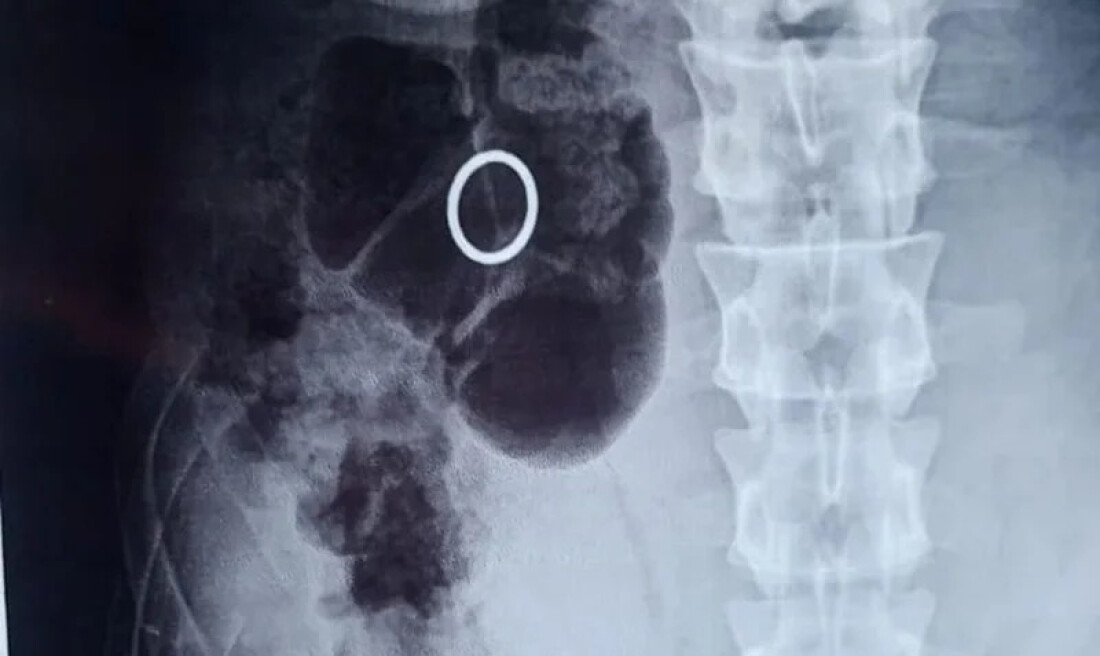

Ainda segundo a PM, imagens de uma radiografia realizada em uma unidade de pronto-atendimento da cidade confirmaram que o suspeito havia engolido o anel.